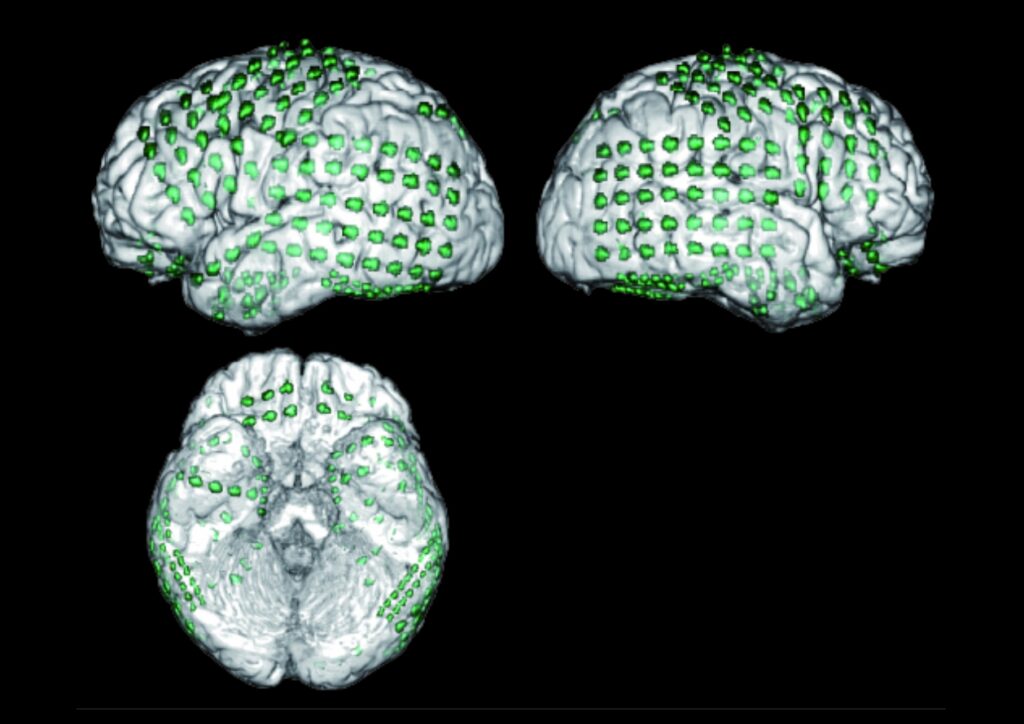

非侵襲的脳活動計測

本講座では、さまざまな脳疾患を対象とした非侵襲的脳計測手法を実施しています。これらの手法は、患者様に身体的な負担をかけずに、脳構造や活動の計測ができることが特徴です。てんかんモニタリングの一環として、頭皮脳波計測を行っており、てんかん発作時の脳波を解析し、てんかん発作のメカニズムの解明や最適な治療方針の策定に役立てています。また、臨床研究や医師主導の治験においては、本学の放射線科学講座、小児科学講座、神経内科学講座と協力し、機能的磁気共鳴画像法(fMRI)やポジトロン断層撮影(PET)を活用して、脳の特定領域の活動を可視化し、認知機能や脳疾患のメカニズム解明に取り組んでいます。